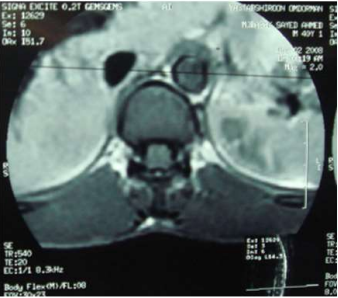

Image (3) Axial MRI of case (1) T1 weighted MRI showing spinal cord expansion and scattered hyperintense patches.

Image (6) Axial MRI of case (6) T1 weighted MRI showing spinal cord expansion and scattered hyperintense patches.

Eight of the ten patients were diagnosed utilizing MRI which showed Dorsal 12 to Lumber 1 or 2 spinal cord swelling with hyper intense patches in T2 images , while the remaining two patient were diagnosed utilizing CT myelogram which showed Dorsal 12 to Lumber 1 or 2 spinal cord swelling.